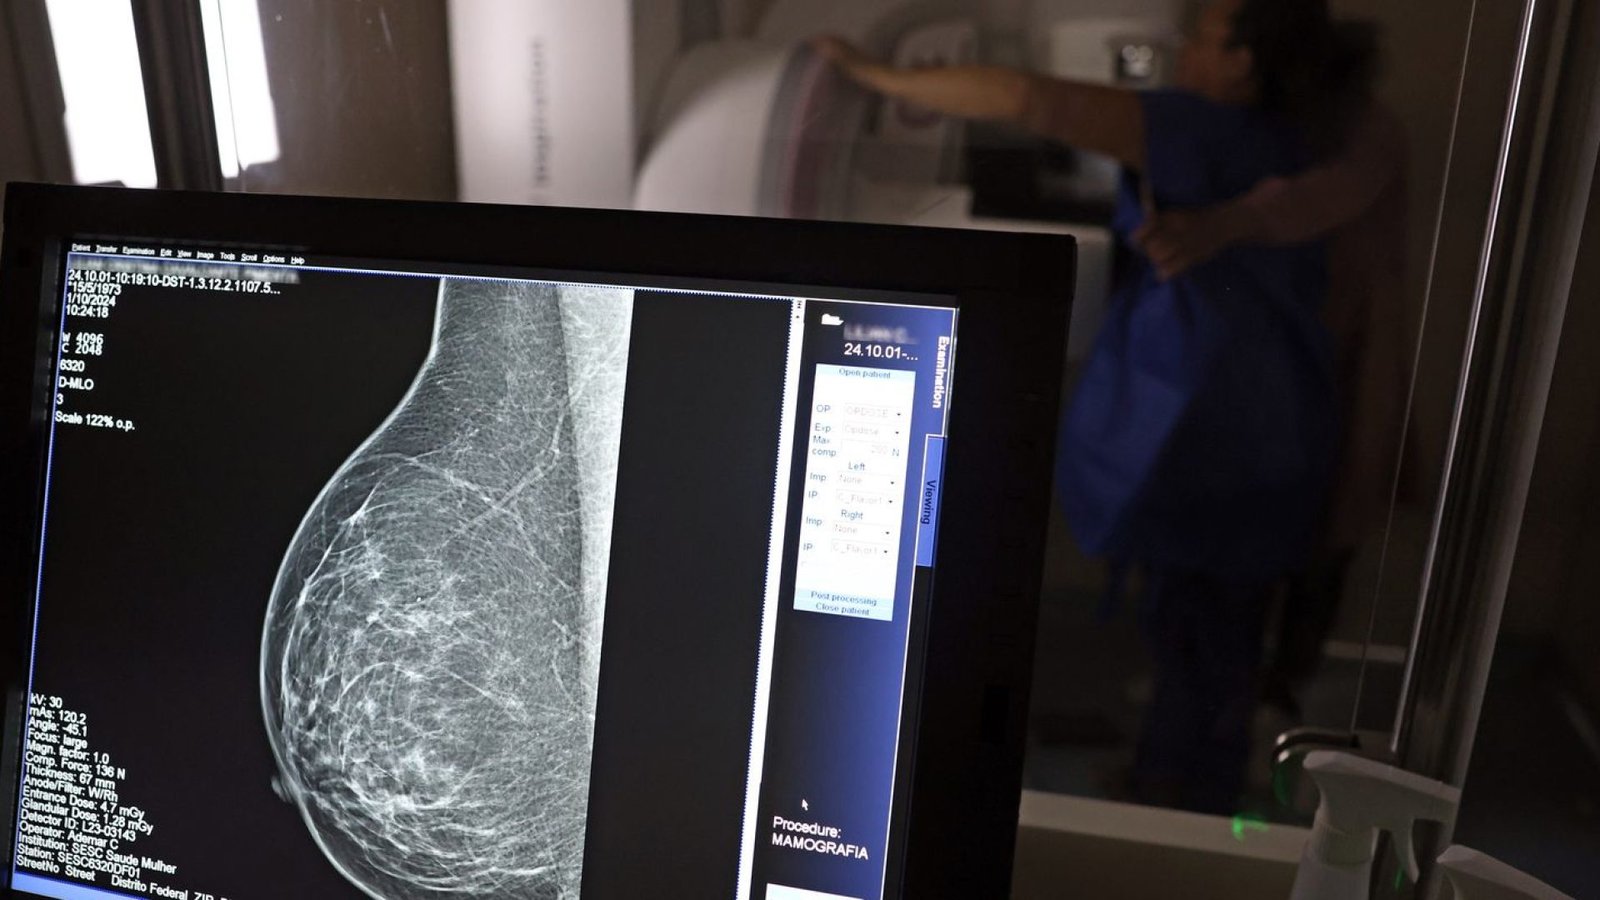

O Ministério da Saúde implementou uma nova diretriz que amplia o acesso à mamografia, via Sistema Único de Saúde (SUS), para mulheres entre 40 e 49 anos, mesmo na ausência de sinais ou sintomas de câncer de mama. A medida considera que 23% dos casos da doença se manifestam nessa faixa etária, e a detecção precoce é crucial para aumentar as chances de cura. Anteriormente, a recomendação era iniciar os exames a partir dos 50 anos.

Dados do ministério apontam que mamografias via SUS em pacientes com menos de 50 anos representaram 30% do total em 2024, totalizando mais de 1 milhão de exames.

Em 2024, o SUS realizou aproximadamente 4 milhões de mamografias para rastreamento e 376,7 mil exames diagnósticos.